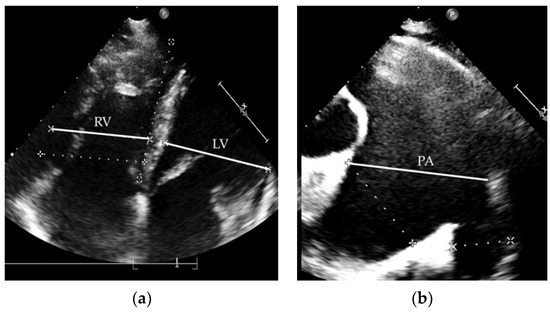

| RHC Parameters | Time of Diagnosis | Before Initiation of the Specific Therapy | 8 Years of Specific Therapy |

|---|---|---|---|

| mPAP (mmHg) | 59 | 90 | 49 |

| PVR (WU) | 8.1 | 12.6 | 6.9 |

| PCWP (mmHg) | 8 | 10 | 13 |

| CO (L/min) | 6.1 | 5.5 | 5.2 |

| Before ST | 1 Year of ST | 5 Years of ST | 10 Years of ST | |

|---|---|---|---|---|

| 6MWT (m) | 575 | 690 | 670 | 630 |

| NYHA class | III | I-II | II | II |

| TR grad. (mmHg) | 80 | 70 | 66 | 50 |

| TAPSE (mm) | 15 | 21 | 29 | 21 |

| PA diameter (mm) | 52 | 56 | 58 | 66 |